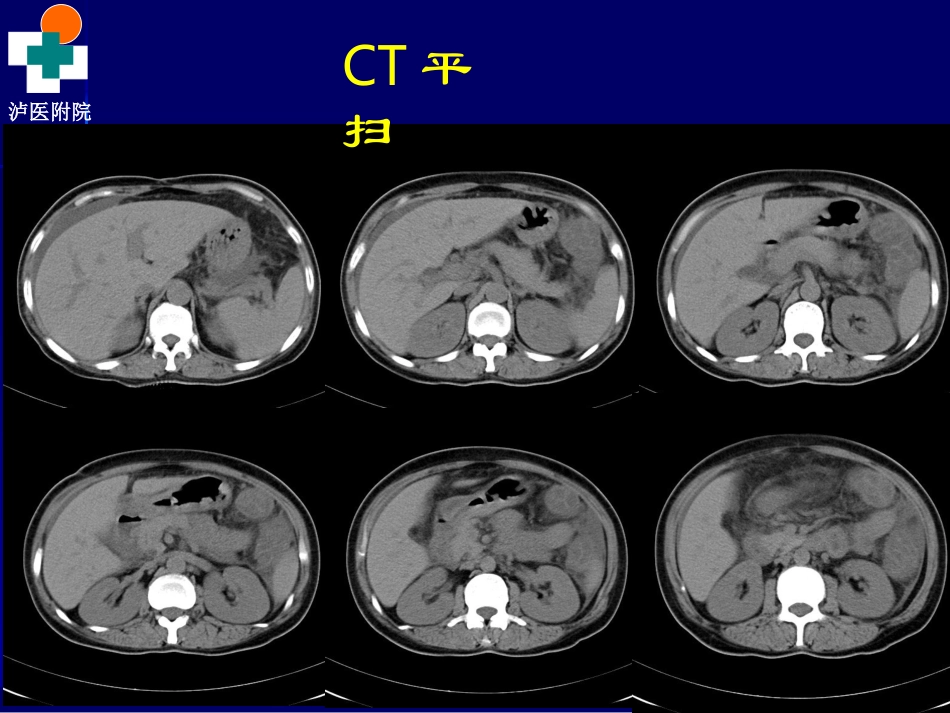

泸医附院THEAFFILIATEDHOSPITALOFLUZHOUMEDICALCOLLEGE院外电解质K+2.06mmol/L胃镜提示:慢性非萎缩性胃炎伴胆汁反流,胃潴留,动脉血气分析K+<2.0mmol/L,BE-8mmol/L泸医附院THEAFFILIATEDHOSPITALOFLUZHOUMEDICALCOLLEGE2013/7/19我院腹部CT平扫+增强提示:1、胃壁及所扫肠道壁明显增厚、水肿,以结肠及空肠明显,肠系膜水肿,腹腔积液。2、肝脏多发小囊肿。脾脏内局限性低密度影,小囊肿?3、目前未见胰腺炎征象。4、胆囊切除。肝内胆管轻度扩张。泸医附院THEAFFILIATEDHOSPITALOFLUZHOUMEDICALCOLLEGECT平扫泸医附院THEAFFILIATEDHOSPITALOFLUZHOUMEDICALCOLLEGE动脉期泸医附院THEAFFILIATEDHOSPITALOFLUZHOUMEDICALCOLLEGE静脉期泸医附院THEAFFILIATEDHOSPITALOFLUZHOUMEDICALCOLLEGE2626//8/20138/2013我院我院CTCT多期增强扫多期增强扫描描泸医附院THEAFFILIATEDHOSPITALOFLUZHOUMEDICALCOLLEGECT影像表现泸医附院THEAFFILIATEDHOSPITALOFLUZHOUMEDICALCOLLEGE泸医附院THEAFFILIATEDHOSPITALOFLUZHOUMEDICALCOLLEGE泸医附院THEAFFILIATEDHOSPITALOFLUZHOUMEDICALCOLLEGE泸医附院THEAFFILIATEDHOSPITALOFLUZHOUMEDICALCOLLEGE泸医附院THEAFFILIATEDHOSPITALOFLUZHOUMEDICALCOLLEGE泸医附院THEAFFILIATEDHOSPITALOFLUZHOUMEDICALCOLLEGE泸医附院THEAFFILIATEDHOSPITALOFLUZHOUMEDICALCOLLEGE泸医附院THEAFFILIATEDHOSPITALOFLUZHOUMEDICALCOLLEGE诊断结果??诊断结果??泸医附院THEAFFILIATEDHOSPITALOFLUZHOUMEDICALCOLLEGE肝脏形态大小未见异常,边缘光整,其内密度欠均匀,肝左叶肝脏形态大小未见异常,边缘光整,其内密度欠均匀,肝左叶见两枚类圆形低密度影,大者约见两枚类圆形低密度影,大者约0.6cm0.6cm位于左外叶,无强化。位于左外叶,无强化。肝内胆管稍扩张,其内未见高密度结石影。胆囊未见显示。脾肝内胆管稍扩张,其内未见高密度结石影。胆囊未见显示。脾脏形态大小尚可,脾脏前份见小圆形低密度影,边界清楚,约脏形态大小尚可,脾脏前份见小圆形低密度影,边界清楚,约0.5cm0.5cm,无明显强化。双侧肾上腺及双肾未见确切异常。膀胱,无明显强化。双侧肾上腺及双肾未见确切异常。膀胱未见充盈,其内见导尿管影,子宫及双侧附件未见确切异常。未见充盈,其内见导尿管影,子宫及双侧附件未见确切异常。直肠、结肠及部分小肠肠管壁明显肿胀增厚,不均匀强化,以直肠、结肠及部分小肠肠管壁明显肿胀增厚,不均匀强化,以升结肠及回盲部肠管为甚,肠系膜水肿,肠系膜血管未见明显升结肠及回盲部肠管为甚,肠系膜水肿,肠系膜血管未见明显异常。腹腔积液,腹腔主动脉旁见多个小淋巴结显示,双侧盆异常。腹腔积液,腹腔主动脉旁见多个小淋巴结显示,双侧盆壁及腹股沟区见多个肿大淋巴结。壁及腹股沟区见多个肿大淋巴结。11、直肠、结肠及部分小肠肠壁明显肿胀增厚,肠系膜肿胀,、直肠、结肠及部分小肠肠壁明显肿胀增厚,肠系膜肿胀,腹腔积液,考虑免疫系统疾病,腹腔积液,考虑免疫系统疾病,SLESLE?炎症性肠病?请结合临?炎症性肠病?请结合临床。双侧盆壁及腹股沟区多个肿大淋巴结。床。双侧盆壁及腹股沟区多个肿大淋巴结。22、肝左叶囊肿。脾脏前份低密度影,脾脏囊肿可能。、肝左叶囊肿。脾脏前份低密度影,脾脏囊肿可能。泸医附院THEAFFILIATEDHOSPITALOFLUZHOUMEDICALCOLLEGE讨论系统性红斑狼疮泸医附院THEAFFILIATEDHOSPITALOFLUZHOUMEDICALCOLLEGE系统性红斑狼疮(SLE)部分病例以消化道症状为首发,常被误认消化道疾病。发病可急可缓,临床表现多种多样。早期轻症的患者往往仅有单一的不典型表现,如不早期诊断、治疗,可引起肠穿孔和肠坏死,造成严重后果。泸医附院THEAFFILIATEDHOSPITALOFLUZHOUMEDICALCOLLEGE临床表现SLE以消化道症状为首发表现时,临床表现不典型,易于误诊、漏诊及误治,主要是因为肠系膜血管炎症引起胃肠道血供不足而导致缺血性肠病表现。绝大多数患者以腹痛首发或以腹痛为主要表现,可伴有腹泻、腹胀、恶心、呕吐等,严重者可有消化道出血,甚至发展为肠梗死及肠穿孔等急腹症。但有少数患者以顽固性腹泻...